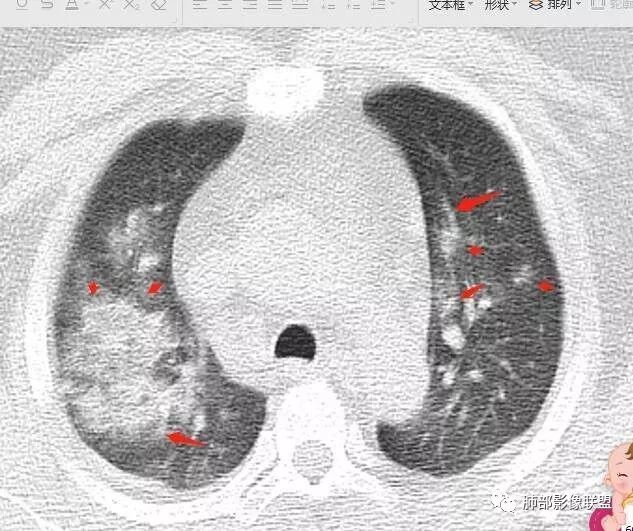

青年男性、急性病史、发热、咳嗽、常规抗炎无效病灶沿支气管血管束分布  GGO+实变边界模糊部分沿胸膜下分布哪几种可能?

南边:1、感染:间质分布——病毒、支原体,支原体一般树芽征明显,累及小气道多,而且临床轻,不太支持2、血管炎,需要相关病史3、肺水肿:心脏不大,无胸水、无中央间质增厚、小叶间隔增厚,不太支持4、PAP,病史影像表现都不支持初学者:可能是病毒,但是好像并不是我们常见的流感病毒实变为主,腺病毒?就是太多灶了一点

重症流感的定义出现以下情况之一者为重症病例1.持续高热>3天,伴有剧烈咳嗽,咳脓痰、血痰,或胸痛2.呼吸频率快,呼吸困难,口唇紫绀;3.神志改変:反应迟钝、嗜睡、躁动、惊厥等4.严重呕吐、腹泻,出现脱水表现;5.合并肺炎6.原有基础疾病明显加重。危重症流感的定义出现以下情况之一者为危重病例1.呼吸衰竭2.急性坏死性脑病3.脓毒性休克4.多脏器功能不全5.出现其他需进行监护治疗的严重临床情况。重症流感病毒肺炎的肺部影像以双肺多发磨玻璃影及实变影为主要表现,可合并少量胸腔积液,典型的H1N1双肺外带分布为主。随病程发展,部分患者出现实变及纤维化临床表现早期流感样症状:咳嗽、咳痰、发热、咽痛、全身酸痛。主要临床表现:肺炎、ARDS。患者咳嗽、咳痰、呼吸困难、氧饱和度低,发热、咽痛、全身酸痛,神志异常。甚至呼吸衰竭、休克,多器官衰竭等等。相关链接https://m.qlchat.com/topic/details?topicId=280000451285864

起病突然,高热,双肺多发磨玻璃影及实变影,胸膜下分布为主,不具有肺门分布优势,也没有小叶间隔增厚,一般会首先考虑病毒感染,尤其是甲流。